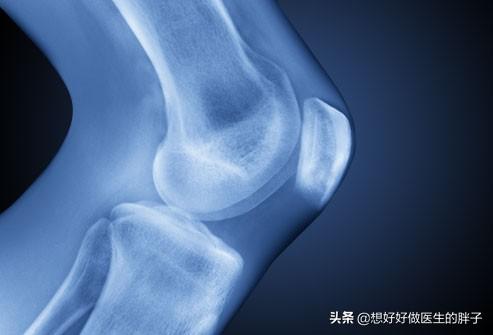

●J'ai un problème avec mes articulations... Cette affection est surtout observée chez les personnes âgées, et il est important de savoir que lorsque l'on a plus de 60 ans, les risques de développer des modifications arthrosiques sont très élevés.Chez les personnes âgées de 63 à 70 ans, 27 % présentent des signes d'arthrose du genou à l'imagerie, et ce chiffre passe à 44 % chez les personnes âgées de 80 ans et plus.. Ainsi, lorsque les articulations d'une personne commencent à développer de l'arthrose, le cartilage de la cavité articulaire s'est usé et déchiré, et même, chez certains patients, un petit resurfaçage osseux s'est formé, de sorte que marcher avec une articulation problématique pendant une longue période après des repas excessifs peut aggraver les changements arthrosiques et entraîner des douleurs dans les articulations.

adresseSi vous avez plus de 45 ans et que vous ressentez déjà des douleurs articulaires importantes en marchant après les repas, il est recommandé de vous rendre à l'hôpital pour une radiographie de l'articulation du genou afin de déterminer s'il y a un problème au niveau de l'articulation.Par la suite, adaptez le temps et la fréquence de la marche après les repas en fonction de l'état des articulations。

Si le patient est plus âgé, qu'il a déjà plus de 60 ans, qu'il a subi un examen radiographique et que les articulations présentent une dégénérescence évidente, marcher pendant une heure après les repas peut être un peu trop long. Il est recommandé d'ajuster la durée à 30 minutes, d'observer si la douleur diminue ou disparaît, de contrôler la quantité de marche quotidienne entre 4 500 et 6 000 pas environ, de ne pas marcher trop longtemps, d'observer les symptômes pour voir s'ils diminuent, et si les symptômes ne peuvent toujours pas être soulagés, il peut être nécessaire de se rendre à l'hôpital pour un traitement systématique. Si les symptômes ne peuvent toujours pas être soulagés, il peut être nécessaire de se rendre à l'hôpital pour un traitement systématique.